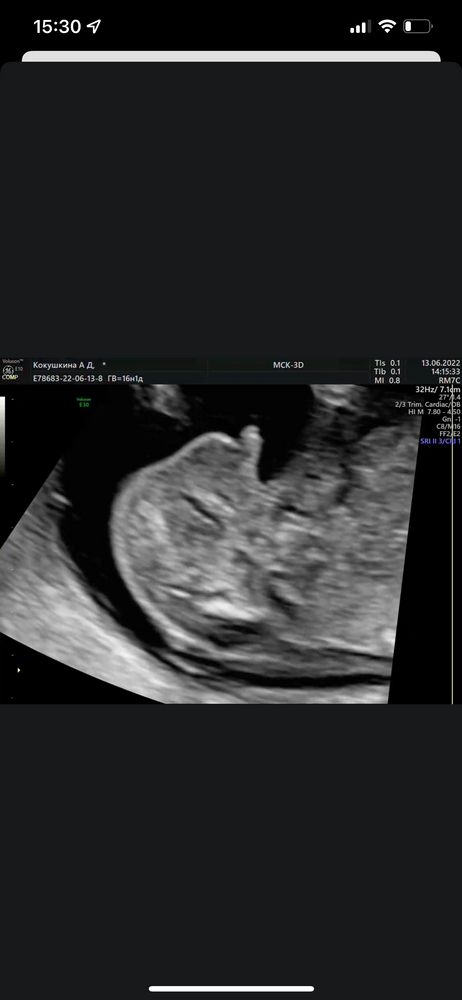

Узнали пол малыша в 16-17 недель🥰

На первом и правда не видно половой бугорок.

Поздравляюююю😍😍😍🌸🌸🌸 это уже 3 пост, где пишут, что по первому скринингу возможно девочка, по второму уже точно мальчик😂 у меня тоже так получилось🤗🤗🤗